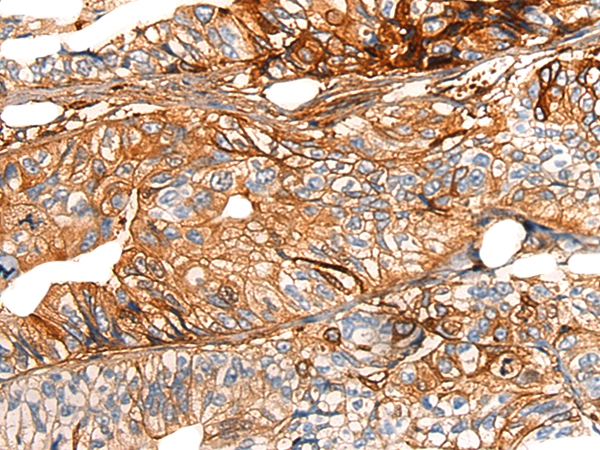

The image on the left is immunohistochemistry of paraffin-embedded Human gastric cancer tissue using 46541(COX6A2 Antibody) at dilution 1/20, on the right is treated with synthetic peptide. (Original magnification: x200)